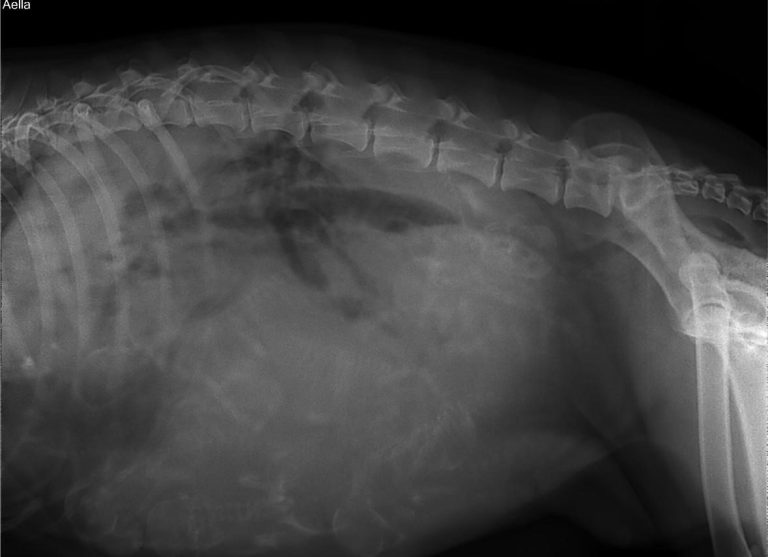

Heute, an Tag 56 haben wir eine Übersichtsaufnahme gemacht und konnten 9 Welpen zählen. Bei dem Umfang, den Aella mittlerweile misst war eine ähnliche Anzahl Welpen wohl zu erwarten gewesen. Wir freuen uns riesig, dass die Welpen dieses Mal Spielkameraden haben und bereiten langsam alles für die Niederkunft vor und genießen die Ruhe vor dem Sturm.

Am Samstag, den 12. Juli setze um 10 Uhr die Geburt ein und nach kurzer Zeit war auch schon der erste Rüde da. Um 17 Uhr kam dann Welpe Nummer 9 auf die Welt und wir waren dankbar, dass alle Welpen gesund und munter auf die Welt gekommen ist. Um 19 Uhr wurden wir dann von Welpe Nummer 10 überrascht! Wie schon vermutet, hatte sich auf dem Röntgen noch ein Welpe versteckt und überraschte uns zuletzt. Wir freuen uns also über 6 Rüden und 4 Hündinnen und stellen uns auf turbulente Wochen ein!